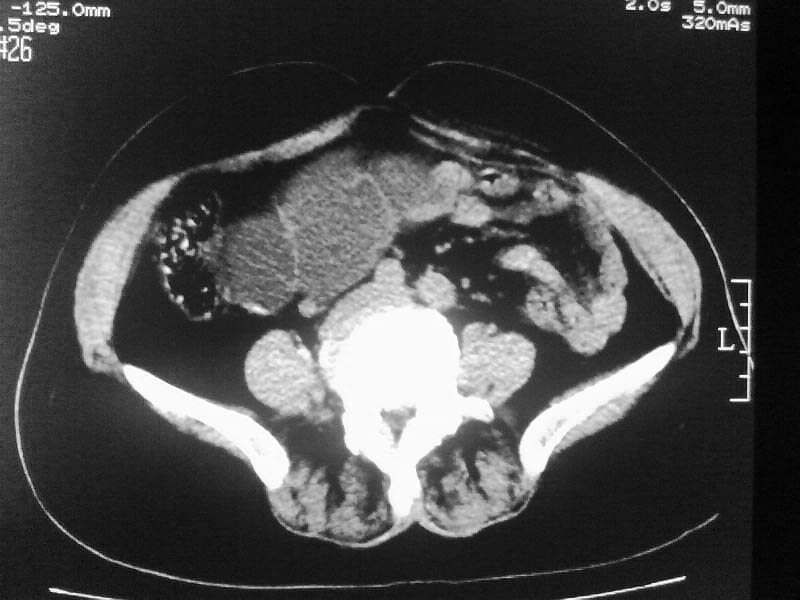

标题: CT20044:女,45岁,腰痛2年,双肾结石,右输尿管结石,右肾重度积 [打印本页]

标题: CT20044:女,45岁,腰痛2年,双肾结石,右输尿管结石,右肾重度积

加扫下输尿管和膀胱吧,先排除下面的大结石所致的积水;

再排除下面的压迫性病灶;

不像普通的积水,密度像是积脓;

多囊肾可以排除。

支持双肾结石、右输尿管上端结石,右肾重度积水

支持 右肾结石、右输尿管上端结石,右肾重度积水。

双肾结石、双输尿管结石并右肾积水。